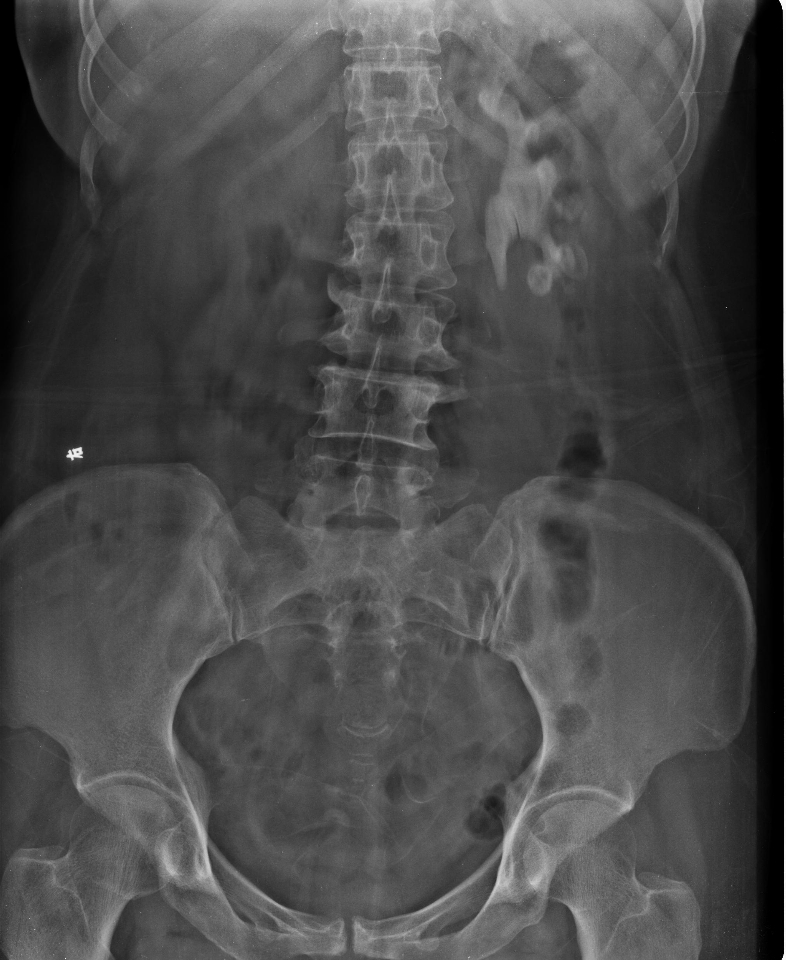

碎石前典型病例1                  碎石后典型病例1

碎石前典型病例2                  碎石后典型病例2